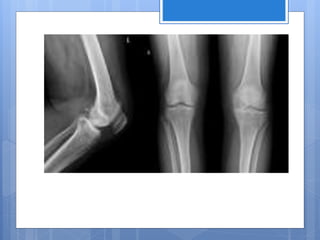

El cartílago es un tejido conectivo elástico y resistente formado por células y fibras que proporciona fuerza y flexibilidad a las articulaciones. Está compuesto principalmente de condrocitos y carece de vasos sanguíneos, por lo que obtiene nutrientes a través de la matriz celular. Existen tres tipos principales de cartílago: el cartílago hialino, el más abundante y rosado; el fibroso, con fibras de colágeno densas; y el elástico.